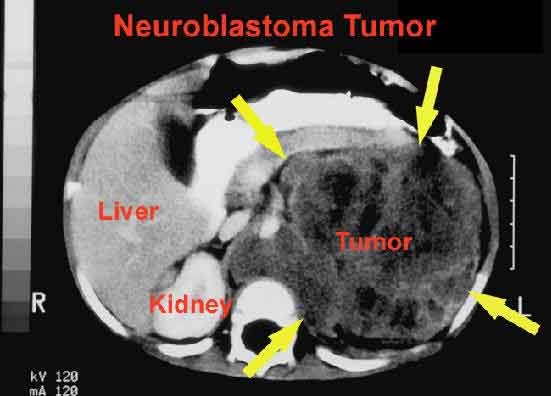

L’alterazione di un gene, l’ML01, e’ collegata all’insorgenza del neuroblastoma. Il passo avanti nella lotta al tumore solido, che colpisce i bambini in eta’ prescolare, arriva da un gruppo di ricercatori europei e statunitensi, guidati dal dottore John Maris del ‘Children Hospital di Filadelfia’, che ha scoperto il gene MLO1 che, alterandosi, puo’ causare questo tipo di cancro molto raro. “Il tumore”, ha detto l’ex primario di Oncologia dell’ospedale Gaslini di Genova, Bruno De Bernardi “e’ la prima causa di mortalita’ per i bambini. In Italia sono 1.500 i casi di tumori che ogni anno colpiscono pazienti in eta’ prescolare. Il 9% di questi (125-130 minori) sono affetti da neuroblastoma e solo il 50% guarisce”. Allo studio, che e’ stato pubblicato sulla rivista scientifica inglese ‘Nature’, ha partecipato il docente di Genetica medica dell’universita’ ‘Federico II’ di Napoli, Achille Iolascon, e un ricercatore dell’ateneo partenopeo, Mario Capasso.

“Abbiamo analizzato il dna di 2.251 pazienti malati e 6.097 bambini sani”, ha spiegato Iolascon, “e scoperto che nei pazienti affetti da neuroblastoma questo gene e’ alterato. Oggi la diagnosi arriva spesso troppo tardi, anche perche’ molti medici tendono a escludere una patologia cosi’ grave in un bambino. Ora sara’ possibile accelerare i tempi e pensare a nuovi farmaci che possano curare questo tumore, senza ricorrere alla chemioterapia o all’intervento chirurgico”. L’alterazione del gene MLO1, pero’, “e’ solo una delle tante cause che possono portare al neuroblastoma”. Per questo, chiarisce Iolascon, “e’ fondamentale proseguire gli studi, anche perche’ la scoperta che presentiamo oggi puo’ essere utile nella cura di altri tumori. Purtroppo i nostri fondi ci bastano solo per sopravvivere. Senza l’aiuto dell’America non ce l’avremo fatta, visto che sono stati investiti milioni di dollari”. Un contributo “piccolo, ma significativo”, e’ arrivato da Open, l’associazione di genitori che finanzia progetti di oncologia pediatrica attraverso donazioni e borse di studio per i ricercatori. Altro aiuto dal Centro di ingegneria genetica (Ceinge) di Napoli, che ha messo a disposizione dei ricercatori macchinari e tecnologie, riducendo sensibilmente i costi per i due ricercatori campani. (AGI) .